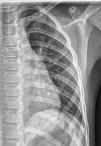

The chest radiograph performed at the outpatient level on account of a previous episode of respiratory illness revealed the presence of a mass compatible with bifid rib (Fig. 1). A computed tomography scan of the thorax (Fig. 2) confirmed the diagnosis and the absence of adjacent abnormalities. The approach to management was conservative with annual followup in the pediatric surgery clinic.